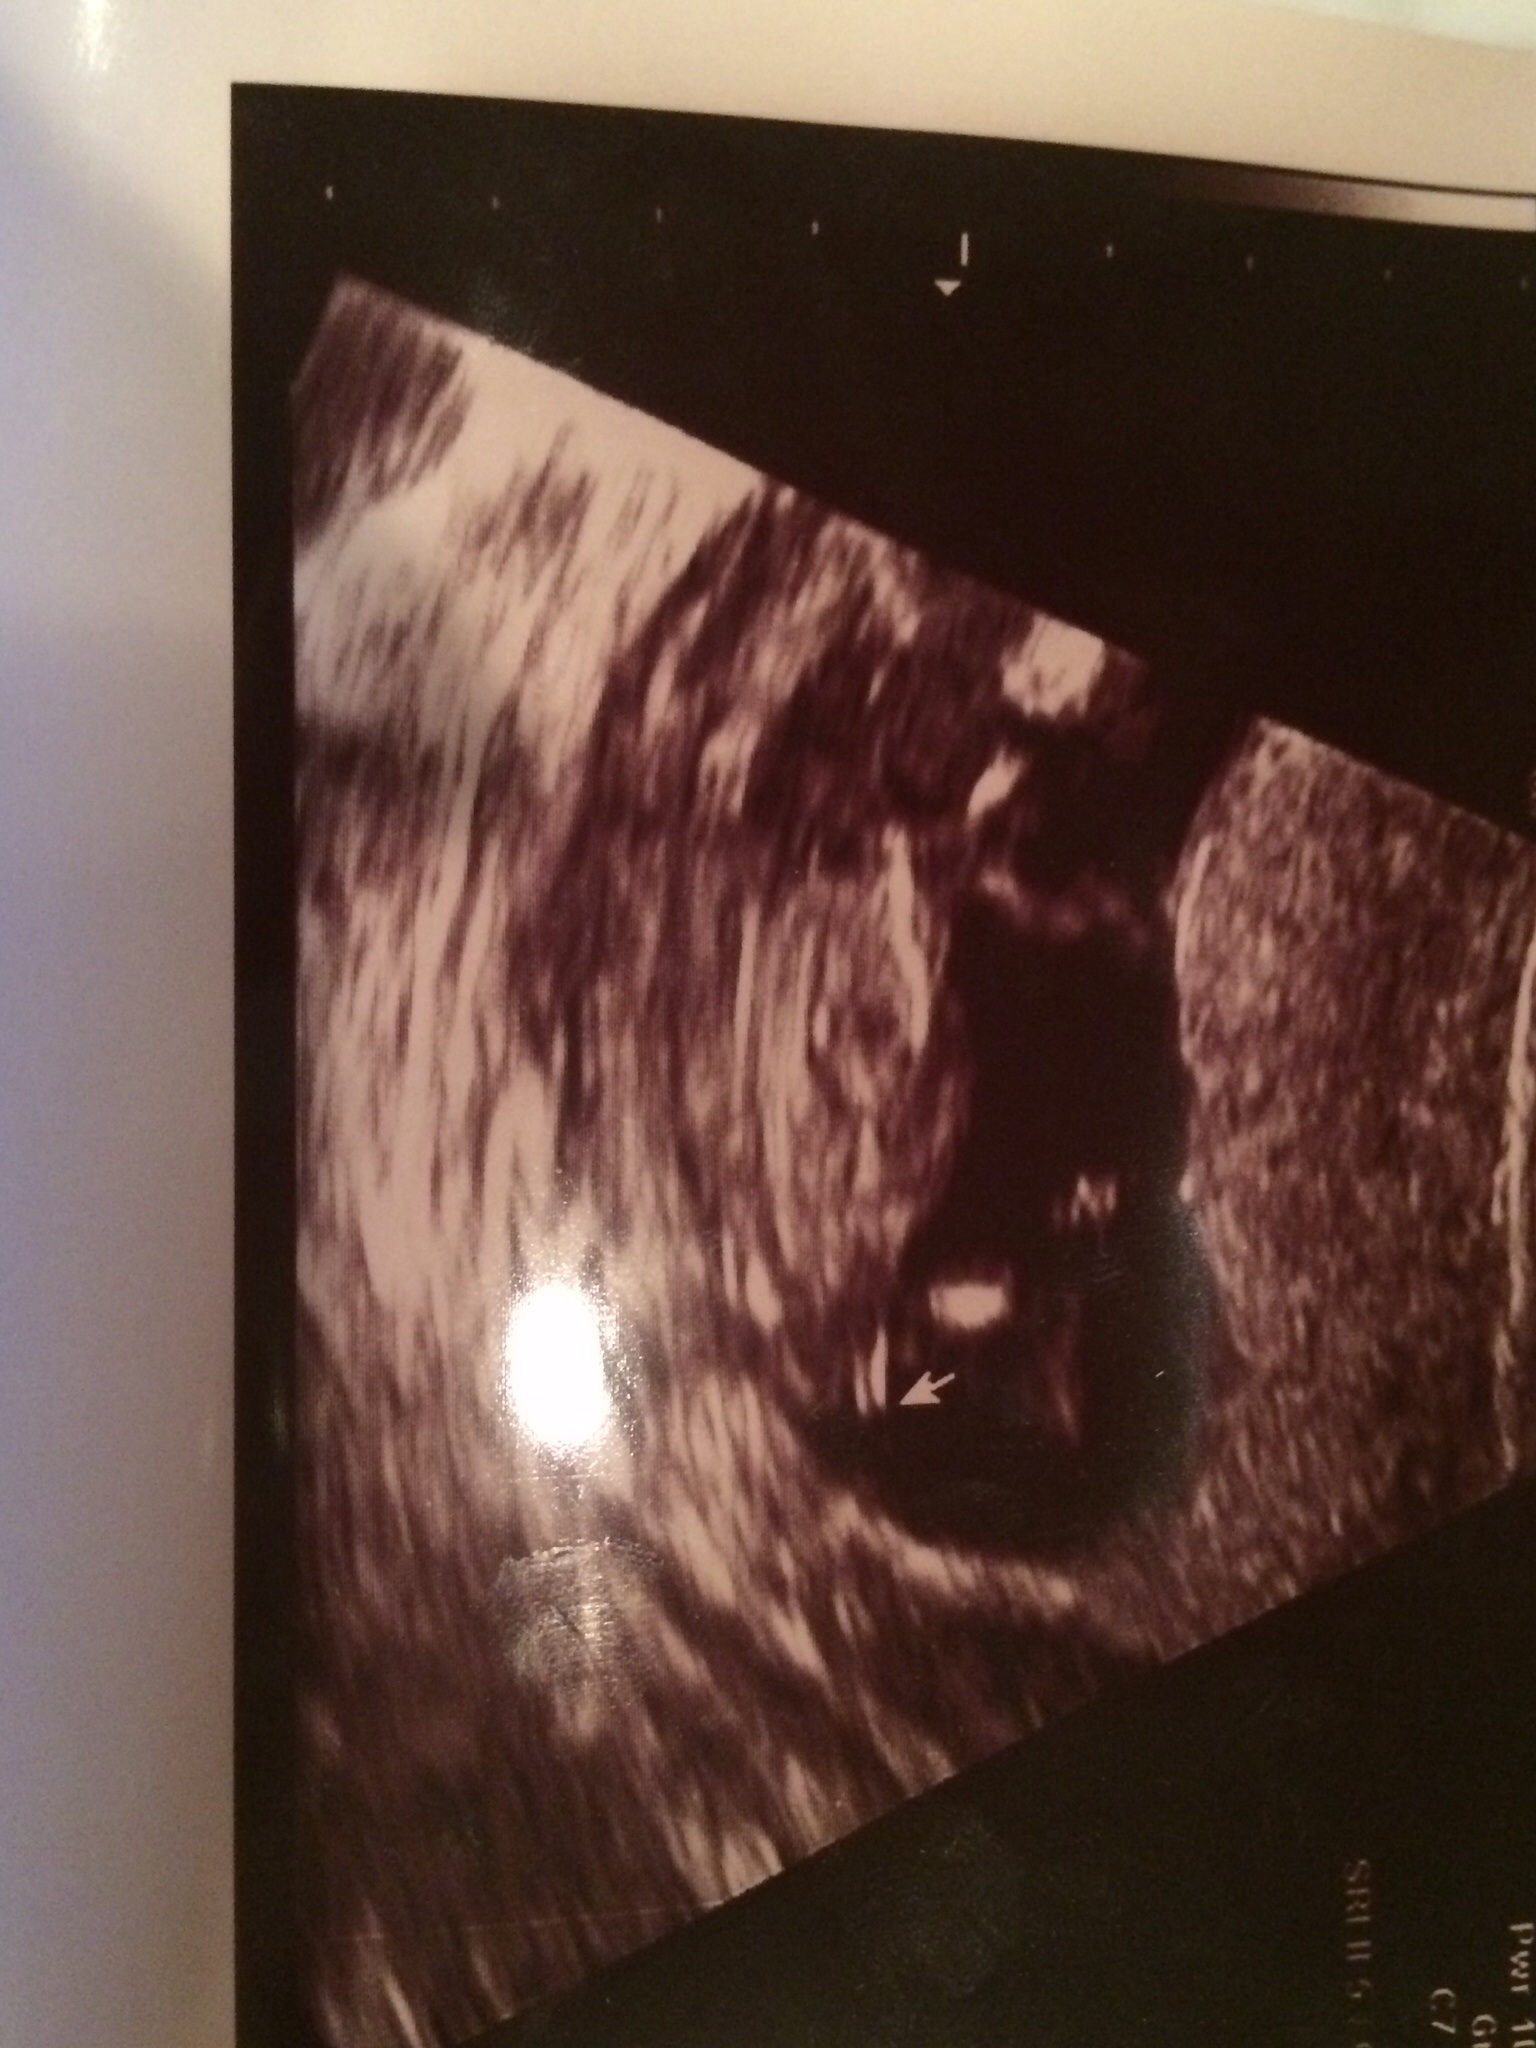

Attachment 20083 Attachment 20084 Pic taken 12w 4 days